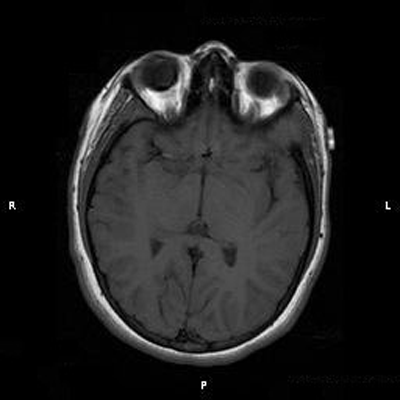

Clinical information: The patient was a 13 year-old girl who presented with worsening headache and some difficulties with memory, concentration and attention. MRI studies disclosed a 2.1 x 1.9 x 1.8 cm enhancing mass in the left temporal bone and sphenoid wing. The mass extended intracranially and abuts the left temporal bone accompanied by dural enhancement at that location. There is also extension through the bone into the submuscular temporal region. The following photos are taken from representative regions of the lesion. Panel 1 and 2 are CT scans at soft tissue and bone density respectively. Panel 3 and 4 are T1 weighed images without and with contrast respectively. Pandl 5 is proton density image. Panel A to D are cytologic (squash) prepartion for intra-operative consultation. Panel E and F are frozen sections for intraoperative consultation. Panel G to L are paraffin embedded sections.